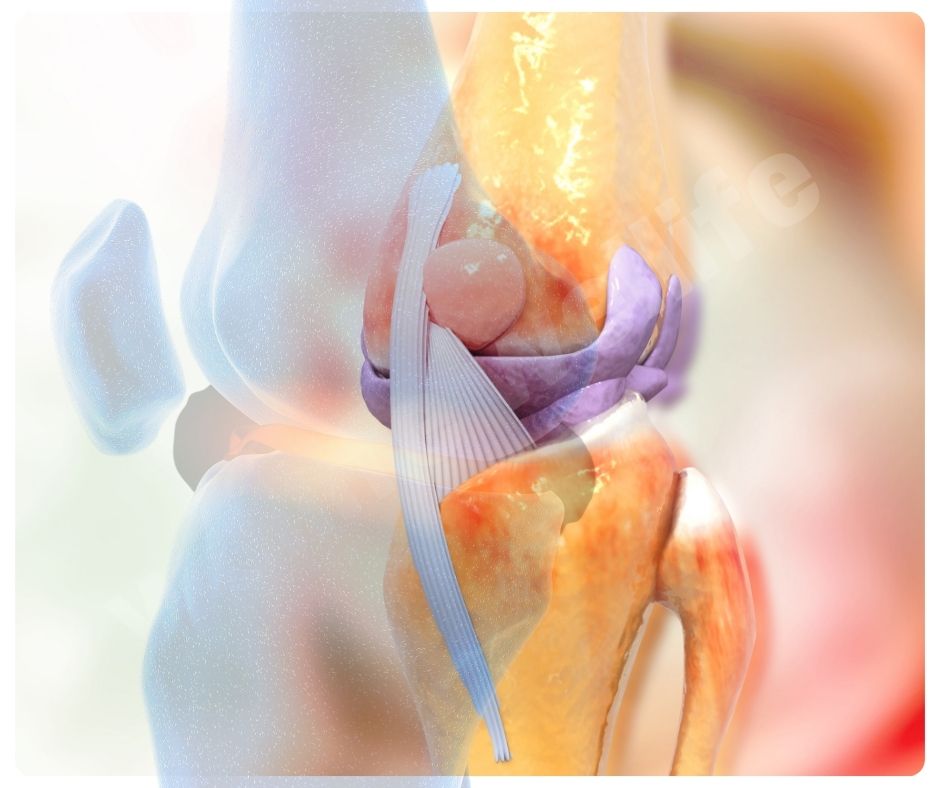

염증 감소

염증 감소는 관절염 환자에게 특히 중요한데요, 염증은 관절 통증과 강직을 유발하는 주요 원인 중 하나이기 때문입니다.

- 항염증 작용: 콘드로이친은 염증 매개체의 생산을 억제해 염증을 줄이는 효능이 있어요.

- 면역 조절: 면역 체계의 과민 반응을 조절해 염증을 완화합니다.